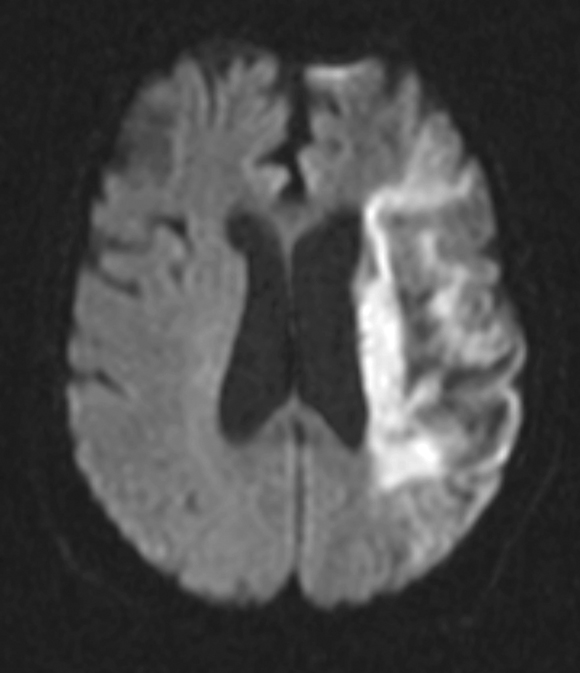

AF predisposes to the formation of blood clots within the left atrium (LA) and particularly the left atrial appendage (LAA) (Box 3), and these may embolise to the systemic circulation. Consequently, AF is an independent risk factor for cardioembolic ischaemic stroke. Although most strokes in people with AF are embolic from the LA/LAA, about a quarter may originate elsewhere — from the left ventricle, heart valves, and extracranial and intracranial arteries. Cardioembolic strokes in patients with AF are typically larger, associated with higher early mortality, and occur in older patients compared with strokes in patients with sinus rhythm (Box 4).